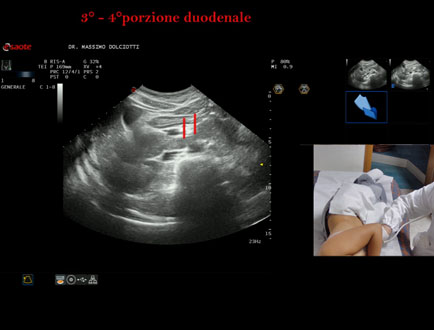

Data inserimento: 19/09/2025

Ecografia del: 10/09/2025

Strumento: Esaote MyLab Eight

Sonda: Convex Multifrequenza 1-8 MHz

Età Paziente: F 24 anni

Motivazione dell'esame:identificazione della terza e quarta porzione duodenale.

Commento all'esame: le immagini ed il video documentano il duodeno ed in particolare la terza e quarta porzione.

Conclusioni: 3° e 4° porzione duodenale (3rd and 4th duodenal portion).

Presentazione: Dr. Massimo Dolciotti - Ancona

Elaborazione digitale: Andrea Dini - Ancona